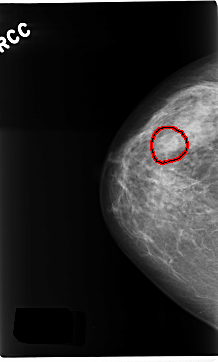

C_0229_1.RIGHT_CC

FILE: C_0229_1.RIGHT_CC.OVERLAY

TOTAL_ABNORMALITIES 1

ABNORMALITY 1

LESION_TYPE MASS SHAPE OVAL MARGINS CIRCUMSCRIBED

ASSESSMENT 3

SUBTLETY 5

PATHOLOGY BENIGN

TOTAL_OUTLINES 1

BOUNDARY